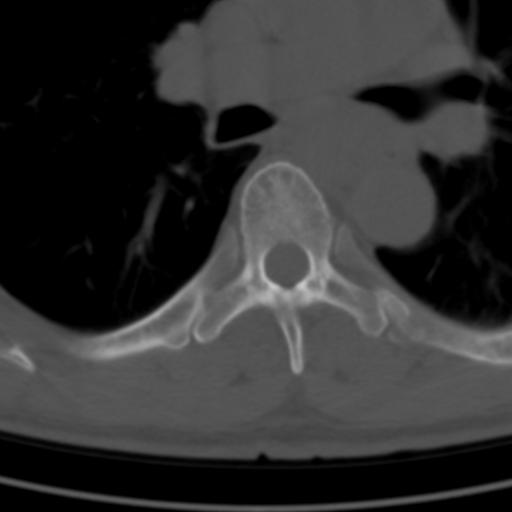

标题: CT25189:胸椎ct,请会诊!

既往食管癌,现行ct检查!

中上段食道癌,椎体轻度退变。

支持中上段食道癌,椎体轻度退变,必要时做ect。